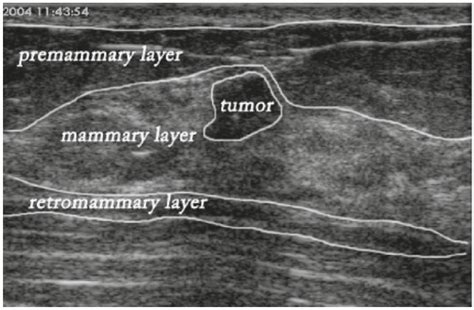

The mechanism behind an Usg Of Breast is based on the principles of sonography. A handheld device called a transducer is moved across the skin of the breast. This transducer emits sound waves that bounce off the structures within the breast and return to the device as echoes. A computer then converts these echoes into real-time images displayed on a monitor.

Interpreting the Results

After the Usg Of Breast is completed, a radiologist analyzes the images to look for specific characteristics. They evaluate the borders of a mass, its shape, and how it interacts with surrounding tissues. While an ultrasound is highly effective at identifying fluid-filled cysts—which are rarely cancerous—it is also used to flag solid masses that exhibit features concerning for malignancy. It is important to remember that not all masses identified on an ultrasound are cancerous. Many turn out to be benign fibroadenomas or normal glandular tissue.